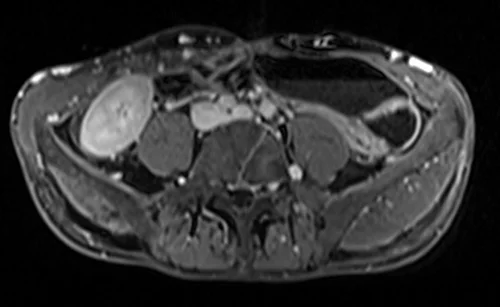

MRV abdomen axial t1 flash post contrast image 2 - MRI